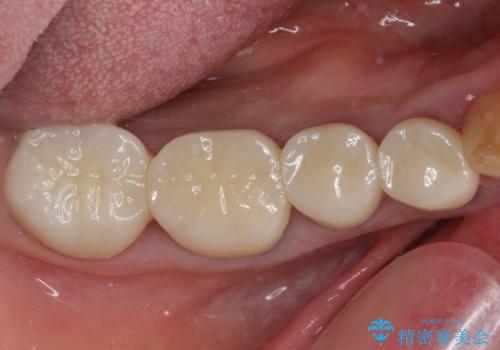

全ての奥歯の銀歯をセラミックに メタルフリー治療

土台に含まれている金属も含め、奥歯の金属は全て除去し、オールセラミッククラウンやセラミックインレーにて治療することとしました。

途中体調を崩されてしまい、その間に仮歯が外れてしまうなど、治療期間が長引いてしまいました。

治療期間はかかってしまいましたが、念願のメタルフリーとなり、患者様には大変満足していただきました。